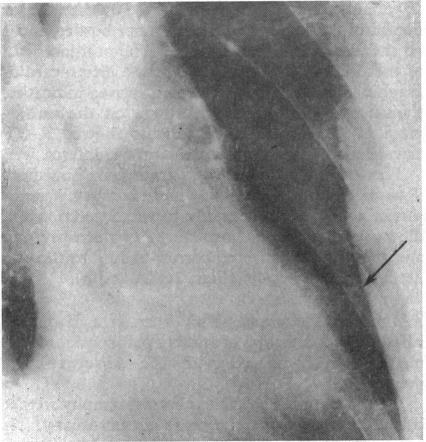

Radiological abnormalities in patients who have survived a myocardial infarction. Their possible relationship to aneurysm formation.

Br Heart J. 1968 Mar;30(2):236-41. doi: 10.1136/hrt.30.2.236.